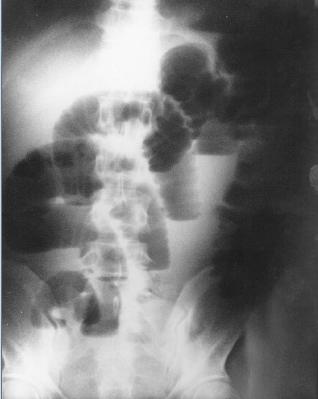

Image en escalier typique de

occlusion de l'intestin grele . L'intestin est tres

dilate depasse 36mm de diametre et les niveaux hydrique se situe en

escalier

au milieu de l'abdomen . |

| Occlusion de l'intestin grele

avec image hydro-arerique du cadre intestinale est

en particuliairement que sa largeur est tres

etroite que la hauteur .et image de

transitionelle Region pelvienne est vite (

n'as pas de air intestinale ) . |